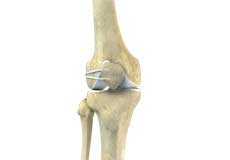

Bones of the Knee

The knee is a hinge joint made up of two bones, the thighbone (femur) and shinbone (tibia). There are two round knobs at the end of the femur called femoral condyles that articulate with the flat surface of the tibia called the tibial plateau. The tibial plateau on the inside of the leg is called the medial tibial plateau and on the outside of the leg, the lateral tibial plateau.

The two femoral condyles form a groove on the front (anterior) side of the knee called the patellofemoral groove. A small bone called the patella sits in this groove and forms the kneecap. It acts as a shield and protects the knee joint from direct trauma.

A fourth bone called the fibula is the other bone of the lower leg. This forms a small joint with the tibia. This joint has very little movement and is not considered a part of the main joint of the knee.